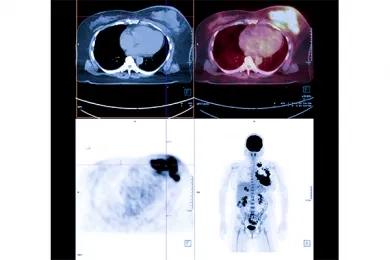

Many different imaging methods can be used in the diagnosis of neuroendocrine tumors, including CT, MR, PET/CT, and ultrasound. PET/CT imaging performed with FDG, a kind of sugar used in the diagnosis of many cancers and in the detection of disease spread, falls short in detecting neuroendocrine cancers. For this reason, special PET/CT scans using smart molecules are used for neuroendocrine cancers. Gallium-68 DOTATATE PET/CT imaging is used to find and image tumor cells in the body at the molecular level. Gallium-68 DOTATATE is accepted as an up-to-date imaging method used for neuroendocrine tumors.